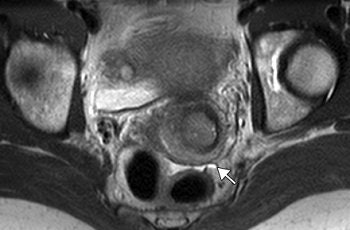

| Transverse T2-weighted MR images in 35-year-old patient with cervical carcinoma obtained with, above, standard sequence (2705/80; imaging time, 4 minutes 3 seconds) and, below, fast sequence (4933/100; imaging time, 39 seconds). Motion artifacts (arrowhead) are absent in image below and moderate in image above; thus, delineation of intact cervical stroma is even better with the fast sequence. Detection of ascites (arrow) is better (in image below). The remaining tissue contrasts and visual SNRs in the two images are comparable. |

According to the results, 27 solid tumors were diagnosed in 24 patients and 12 cystic tumors, or liquid-containing disorders, were found in 10. The visual SNR for the fast sequence was comparable to the standard one in all 33 patients. The tissue contrast between solid tumors and muscle also was comparable. With the fast sequence, there was significantly higher contrast between urine and muscle, between ovarian cysts and ovarian stroma, and between cystic tumors or liquids and muscle.

Motion artifacts were significantly reduced with the fast sequence, and the final MRI diagnosis did not differ between the two sequences. On the downside, the tissue contrast of the zonal anatomy could not be analyzed in 33% of the women.

Most importantly, the imaging time for the fast sequence was 39 seconds versus four minutes and three seconds with the standard sequence.